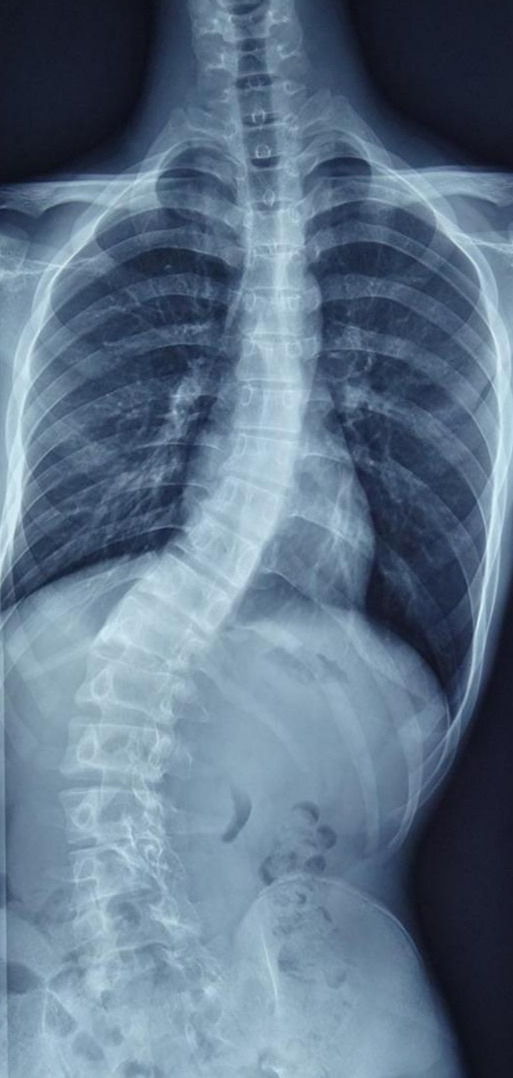

首先让我们看一例青少年脊柱侧弯

这是一名13岁患者,从小脊柱就有些“歪”,但是家长一直未予以重视。随着孩子逐渐进入青春期,身体逐渐长高,脊柱却“歪”的越来越厉害,而且出现了二便*禁失**,从影像学我们发现,他不仅存在脊柱侧弯,还存在许多其他问题。